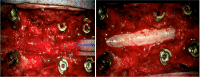

Results: A 65-year old female presented with neurogenic claudication and magnetic resonance imaging (MRI) revealed lumbar spinal stenosis. Following decompressive surgery, she experienced symptom resolution, but three months postoperatively she presented to the emergency department with acute paraparesis. A thoracic MRI revealed a lesion located between T8 and T10 causing severe spinal cord compression. Following emergent laminectomy and en bloc resection, the patient regained function and the lesion was diagnosed as SAL. Our literature review revealed 178 reported cases, with a female and thoracic predominance. The majority of patients underwent surgical treatment, achieving a gross total resection in most cases. Similarly, complete symptom resolution was the most common outcome.